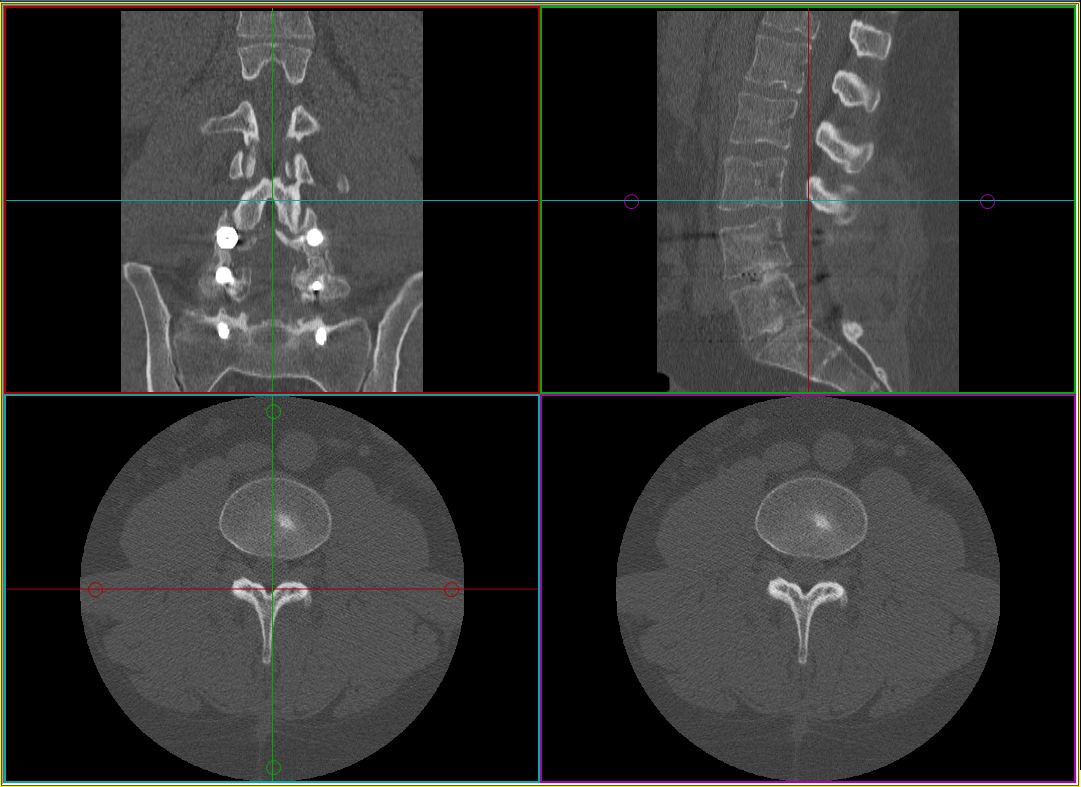

Az MPR létrehozása után a képkocka négy kisebb kockára oszlik. Minden keret egyetlen ortogonális nézetet (szagittális, koronális és axiális), plusz egy ferde szögű nézetet tartalmaz. A ferde képkocka az Eredmények ablak, ezt egy lila lokalizáló jelzi a coronális nézetben. A másik három kocka vezérlőablak. Olyan színkoordinált lokalizálók állnak rendelkezésre, amelyek a vonal színét az adott síkban lévő képet tartalmazó kocka színéhez illesztik. Ezekkel a lokalizálókkal mozgathatja és elforgathatja a ferde képet.